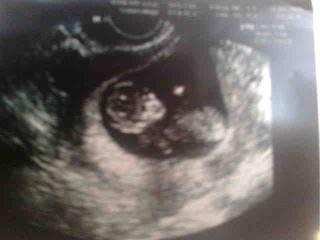

tak som pridala fotku nasho drobca - kuk do albumu 😉

resp. sa to da pridat aj sem, tak skusim 😉

me5 - pekné babo - už teraz taky malý človiečik

zuzana - dakujem, tiez sme vcera s drahym pozerali, ze ani sa verit nechce, ze uz tam je taky hotovy cloviecik. hlavne ze jemu je dobre, ked uz mne nie je 😀